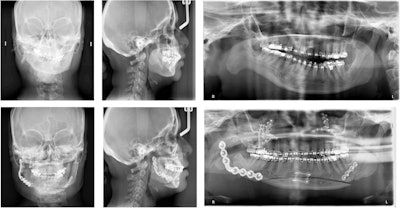

A composite of the patient, showing significant facial asymmetry and malocclusion prior to surgery. All images courtesy of Vajda et al. Licensed under CC BY 4.0.

The patient's presurgery cephalometric radiograph.

The patient's presurgery cephalometric radiograph.In July 2017, the woman visited the oral and maxillofacial surgery clinic due to her poor bite and facial asymmetry. A physical exam revealed that she had a severe 10-mm occlusal cant, only contacting on her right premolars and molars, with a left-sided open bite. This caused a 2-mm incisal display in repose and a negative 2-mm gum display when she smiled. When smiling, the cant caused a 3-mm gingival display on her left and a negative 4-mm gingival display on the right. Also, her chin deviated dramatically to the right of the midline of her face, the authors wrote.